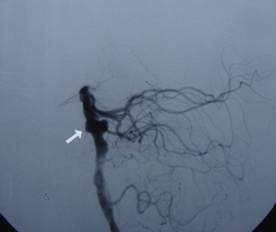

吴某,56岁,因突发昏迷1小时于2月15日急诊入院。入院时深昏迷,呼吸微弱,血氧和血压降低,双侧瞳孔散大,对光反射迟钝,急诊头颅CT提示蛛网膜下腔出血。入院诊断考虑是脑动脉瘤破裂,紧急行气管插管、止血降颅压等抢救措施,同时放射科陆秀伟主任急诊行全脑血管造影,结果提示基底动脉巨大的动脉瘤(图一)。科主任范学政教授紧急组织全院会诊,组成了包括神经外科、重症医学科、呼吸科、放射科专家抢救小组,采取镇静、脱水、抗血管痉挛以及支持和对症等抢救措施,并病情和影像资料传输到神经外科协助医院四川大学华西医院神经外科远程会诊,会诊认为该病人最佳的治疗方案是行血管内介入治疗。经过充分准备,于2月19日在华西医院神经外科张昌伟教授联合我院神经外科医生为患者进行了支架辅助下基底动脉瘤弹簧圈栓塞术,术后行脑血管造影显示动脉瘤完全栓塞(图二)。术后继续予抗血管痉挛等治疗,术后第二天出现呼吸衰竭,肺部感染,后经转入ICU、呼吸科、予以支持、抗感染治疗等综合治疗,术后10天病人清醒,目前患者已经康复出院。

图1:基底动脉瘤